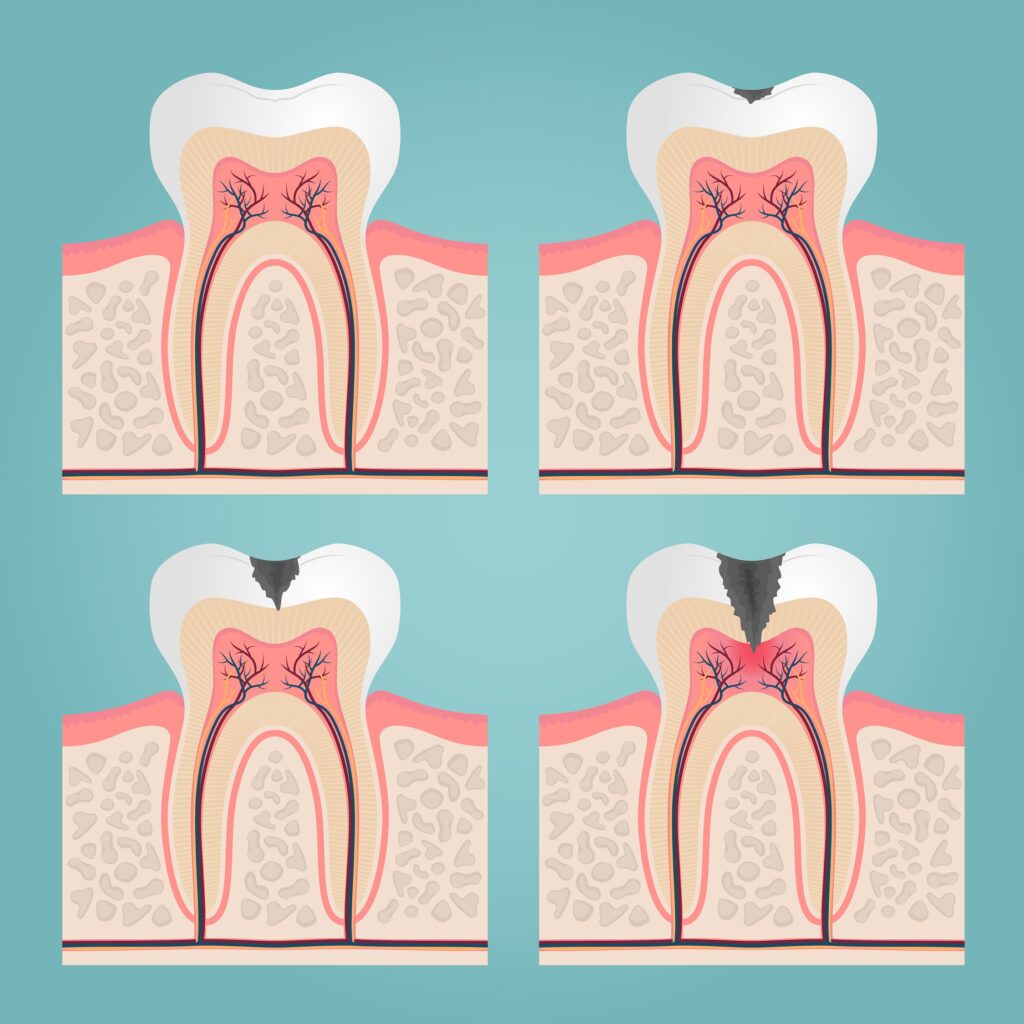

齲齒(Dental caries, Tooth decay),俗稱蛀牙,指的是因口腔中的細菌會以醣類為養分,不斷繁殖並產生菌膜(牙菌斑)附著在牙齒上,同時產生酸性物質腐蝕牙齒表面的琺瑯質。

當細菌進一步侵蝕牙髓腔內部的神經就會產生劇烈疼痛,此時可能就需要進行根管治療(抽神經)甚至拔牙。

細菌產生牙齒表面以至牙髓腔的齲齒進程